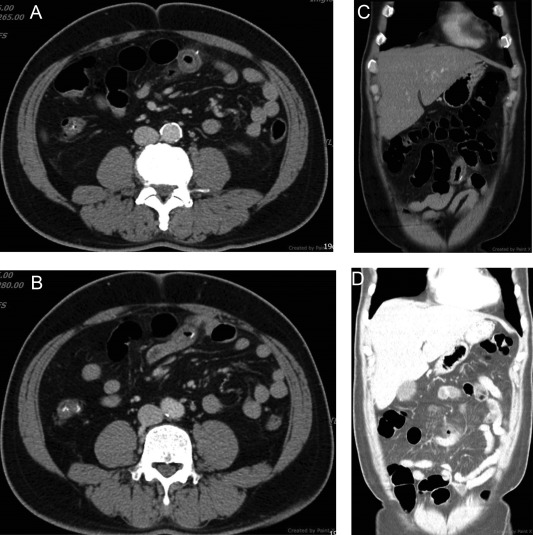

A 54-year-old man presented to the emergency department with worsening lower abdominal pain and anorexia ongoing for 3 days, but without diarrhea or emesis. Upon physical examination, there was local and rebound tenderness over the periumbilical and right lower quadrant areas of the abdomen. Laboratory tests revealed increased inflammatory markers, including a white blood cell count of 13.7 × 103 /μL (90% neutrophils) and a C-reactive protein level of 250 mg/L. An abdominal radiograph in the supine position was obtained but proved unremarkable. The patient was referred for an abdominal ultrasonography (US) where bowel wall thickening was noticed, but it was free of ascites. CT of the abdomen with contrast media demonstrated segmental small bowel wall thickening, adjacent mesenteric fatty stranding, and gas bubble retention. Nearby, one high-density pin-like material penetrating the bowel wall was found (Figure 1 ). Foreign body-induced small bowel perforation was conclusively diagnosed. Based on the patient’s dietary history and the shape of the foreign body, a fish bone was suspected as the cause.

Multidetector computed tomography of the abdomen. (A, B) Axial images ...

Figure 1.

Multidetector computed tomography of the abdomen. (A, B) Axial images demonstrated segmental small bowel wall thickening with fatty infiltration and one radiopaque pin-like lesion penetrating the bowel wall; (C) multiplanar reformation images demonstrate segmental small bowel wall thickening with fatty infiltration; (D) lung window image demonstrates free gas bubbles.